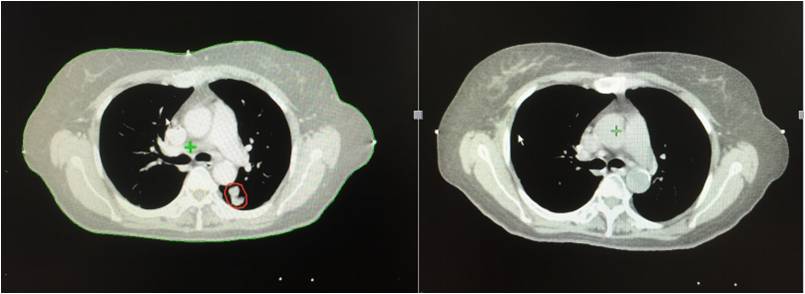

治疗前 治疗后

2013年3月初无明显诱因出现胸闷、气短,活动时加重,伴有间断左侧肩胛区疼痛,无咳嗽、咳痰,无发热、咯血,无盗汗、乏力。2013年4月胸部CT示:右肺占位。4月末在北京大学人民医院行胸部CT增强示:双肺下叶背段恶性病变,考虑肺癌可能性大。5月在*警武**北京总队第二医院行PET/CT检查提示:1.双肺下叶背段斜裂胸膜下高代谢结节,考虑恶性病变,肺癌可能大,双肺多发磨玻璃结节及微小结节,未见明显高代谢,倾向恶性病变;2.右乳外下象限小结节伴代谢,结合临床。

2013年5月入院,肺穿刺病理结果提示:左下肺腺癌。

2013年5月、6月接受四次A45肿瘤治疗治疗四次。2013年10月再次接受全身A45肿瘤治疗1次,右下肺病灶A45肿瘤治疗1次,出院后继续口服易瑞沙靶向治疗。患者肿瘤缩小,几乎消失。患者的状态稳定。